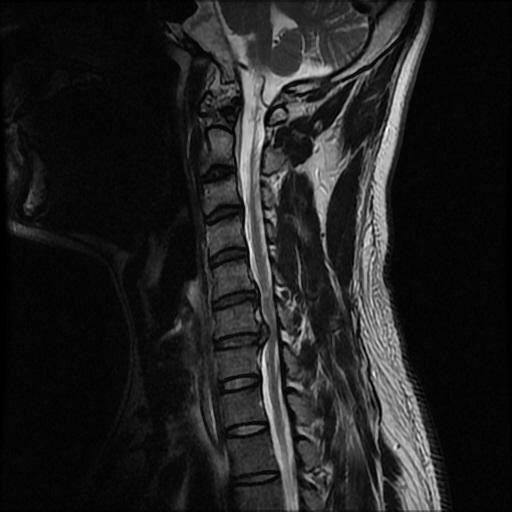

1c.Ż, 1C.ڵӸ 6C.ڸ 6C. κ 6C.ھ Ḳ 6C.ڻ 7C. Ȱ׳ 7C.Ȳġ 7C.ڿʰ 1T.Ȳġ 1T. κ 2T. Ʒκ ()ũ( ߰Ż) ڸ(߹) Ը Ͽ ũ(߰Ż)ġ, , Ḳ ġ ϰ Ѱ 1. ߺ : 3~4 ־ ö ġ ǿ ħġḦ 2009 5 / ǿ ߳ġ ľȭǾ MRIԿ 5~6ũ Ż, 6~7 ũ Ŀ Ż 2. ġ : 6 11 ѹ溴 3ְ Կ ġ Ѿູ ̸ 絵 ۰ ȿ ؽ ϰ |